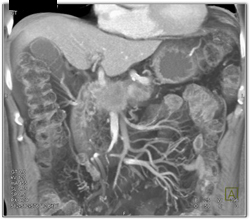

Neurogenic Tumor Simulates A Cystic Tumor